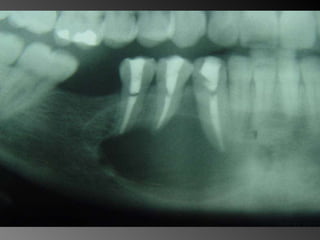

26 - Pacientedo sexo feminino, 30 anos de idade, se apresentou com aumento de volume no corpo da mandíbula, região dos dentes 45, 46 e 47, assintomático e com evolução de aproximadamente 1 ano. Pelo exame clínico constatamos expansão óssea e deslocamento dos dentes 45 e 46 de suas posições normais. Através de radiografia panorâmica observamos uma imagem radiográfica multilocular onde as trabéculas ósseas se encontravam perpendicularmente umas às outras e em outras regiões com aspecto de bolha de sabão. Com base no quadro clínico, o diagnóstico é: a) Ceratocisto e mixoma odontogênico. b) Odontoma composto e ameloblastoma. c) Mixoma odontogênico e ameloblastoma. d) Mixoma odontogênico e odontoma composto. e) Ameloblastoma e ceratocisto.

Mixoma Freqüência: -Segunda e terceira década de vida -Atinge pouco mais a maxila que a mandíbula (região posterior + frequente)

Exame complementares RadiografiaPanorâmica; Radiografia Oculsal; Teste de Vitalidade; Punção Exploratória; Biópsia incisional.

Teste de VitalidadeDente 43: Negativo Dentes 42,44 e 45: Positivo.